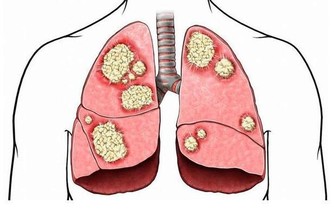

常見對肝功能有影響的藥物包括:

1.抗生素類藥物:如阿莫西林、氯黴素、利福平、磺胺類等;

2.解熱鎮痛消炎藥物:如阿司匹林、撲熱息痛、芬必得、消炎痛等;

3.中樞神經系統藥物;

4.激素類藥物:優降糖、他巴唑、甲亢平、丹那唑;

5.維生素A與菸酸;

6.抗腫瘤藥物;

7.其他藥物:如甲基多巴、心痛定、西咪替丁、消膽胺等。